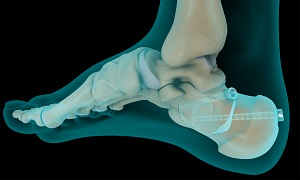

The calcaneus or heel bone is the largest bone in the ankle forming the heel and is situated at the lower back part of the foot. The calcaneus forms the subtalar joint with the talus, which helps in the inward and outward movement of the foot. A fracture of the calcaneus reduces or prevents movement of the subtalar joint. Calcaneus fractures may lead to deformity of the calcaneus bone, irregularity of the subtalar joint, arthritis, and affect the surrounding tendons and nerves of the heel.

Surgery is recommended for intra-articular or displaced calcaneal fractures. The surgical procedure is called an open reduction and internal fixation (ORIF) and is performed under the effect of general anesthesia. Your surgeon will make an incision on the outside of the heel to expose the heel fracture. The fractured heel bones are placed together and fixed in place with a metal plate and multiple screws. This procedure minimizes the chance of developing arthritis and allows inward and outward movement of your foot. Your surgeon will plaster the foot to prevent movement of the ankle for a specified period of time to promote healing.